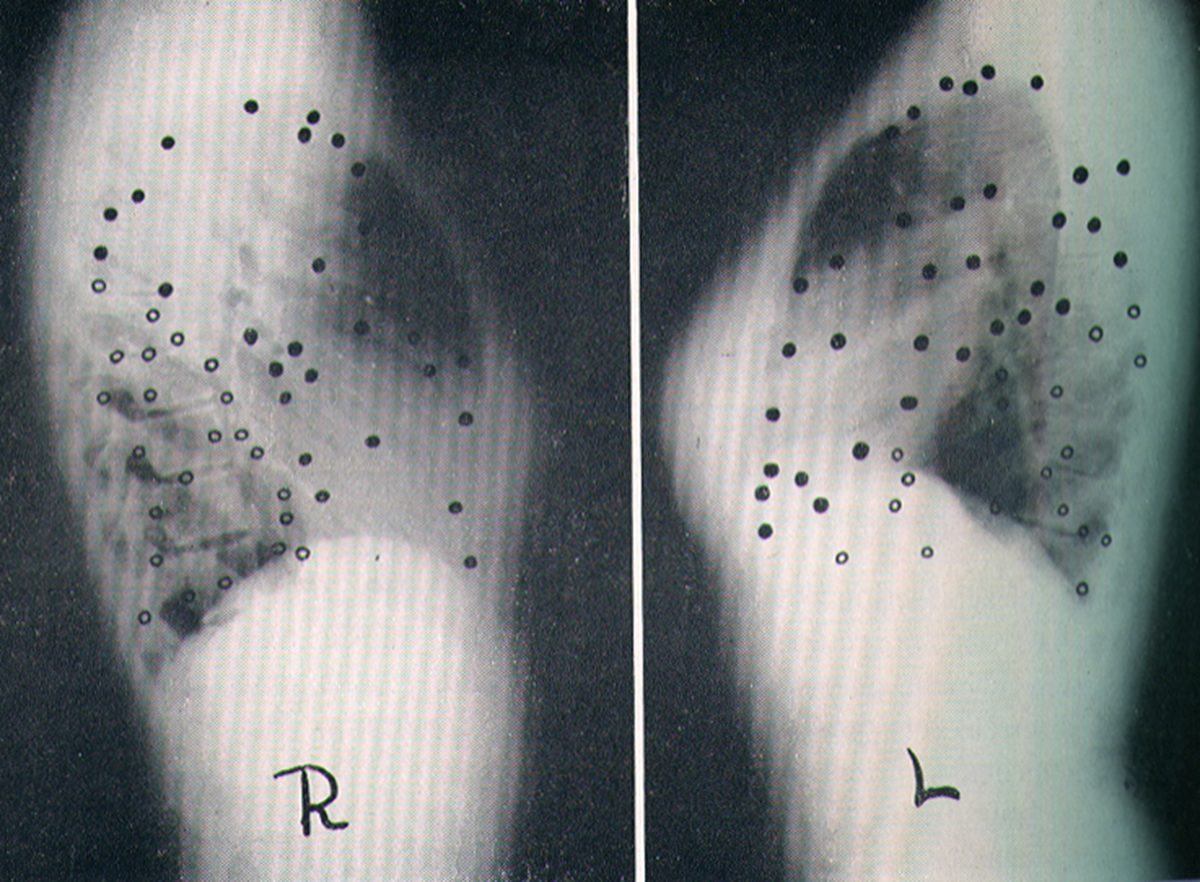

Location Of Primary Calcified Foci

primarily in lower lobesÂ

Location Of Re-Infection Tuberculosis

cluster in upper lobes

Location Of Single Tuberculosis Cavities

RML interestingly spared